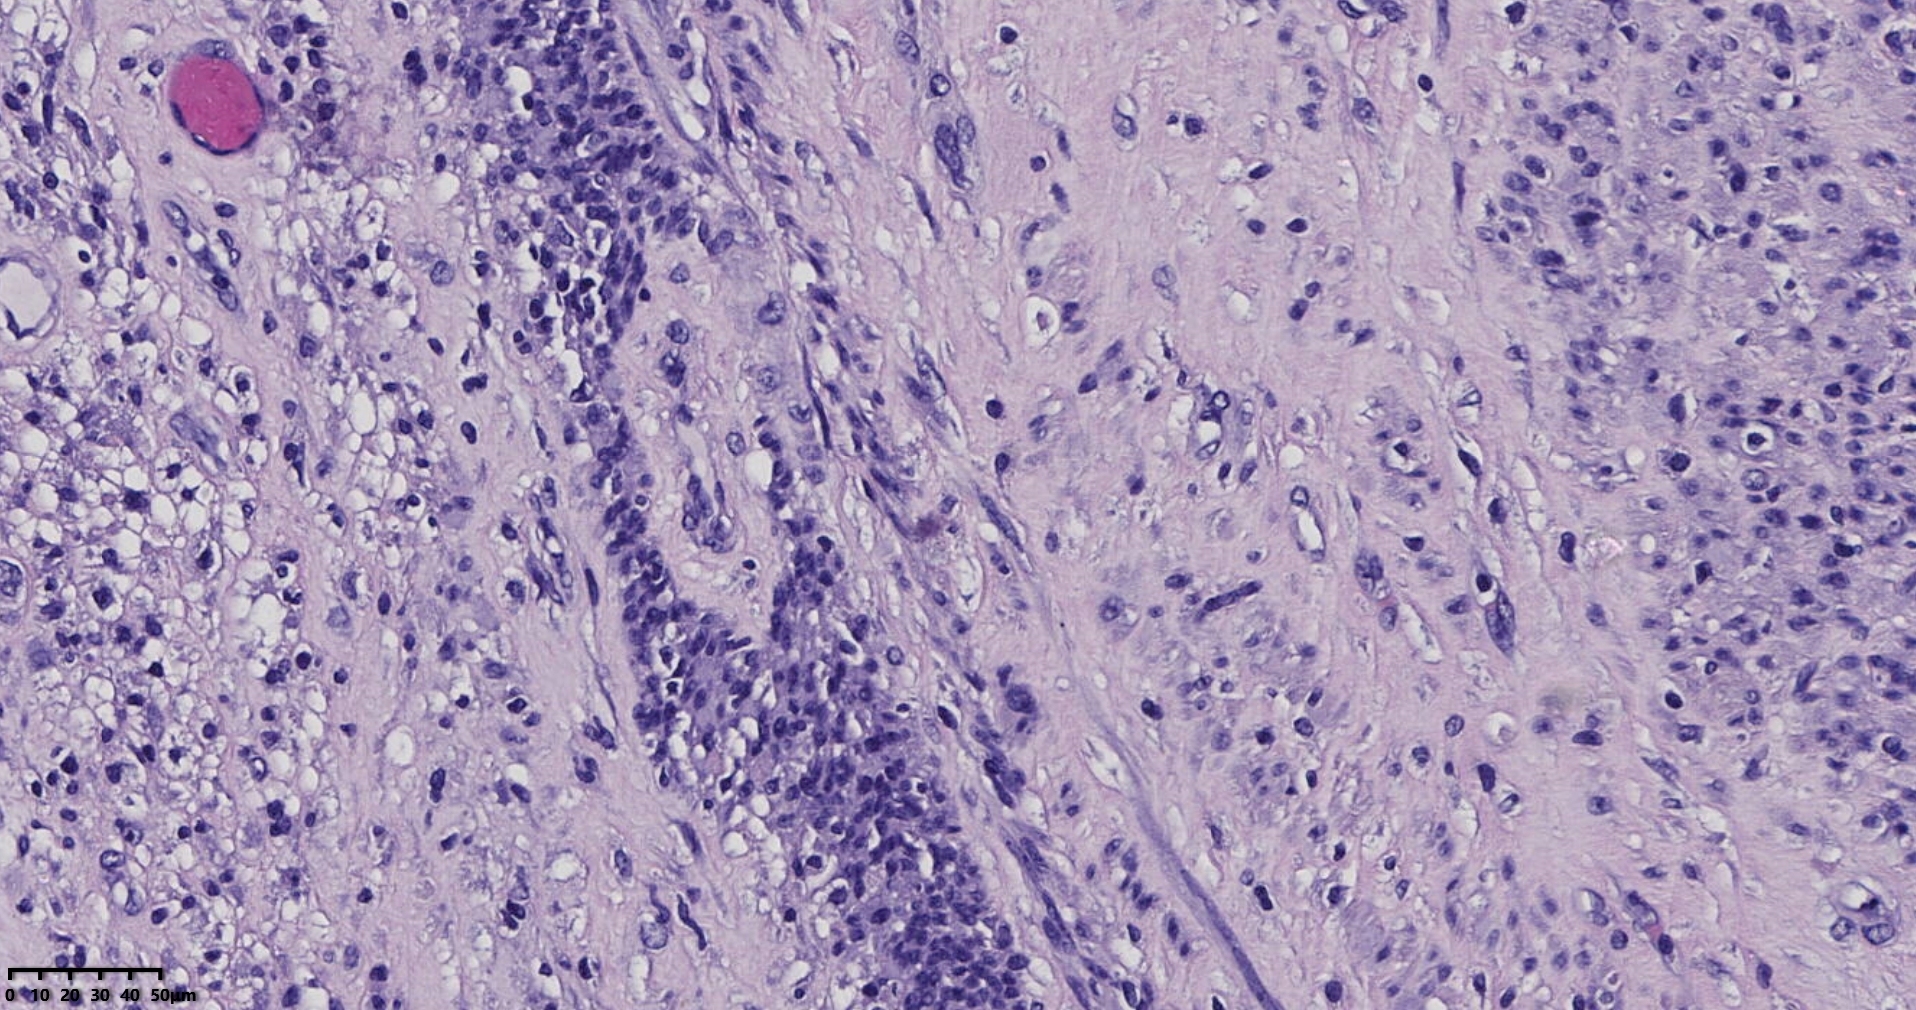

镜下所见小肿物无特殊,大肿物瘤细胞密集,中心区有变性、坏死,瘤细胞核有异型性。大肿物补充取材,发现,部分区域切面灰黄,这个区域,瘤细胞更密集,异型性更显著。肿物边缘有薄层正常平滑肌组织被覆,靠近边缘瘤细胞最密集,局部瘤组织内小血管较丰富。

会诊:考虑平滑肌肉瘤。

北医三院会诊:子宫平滑肌瘤伴红色变性可能性大,建议加做免疫组化及NGS检测进一步明确诊断。